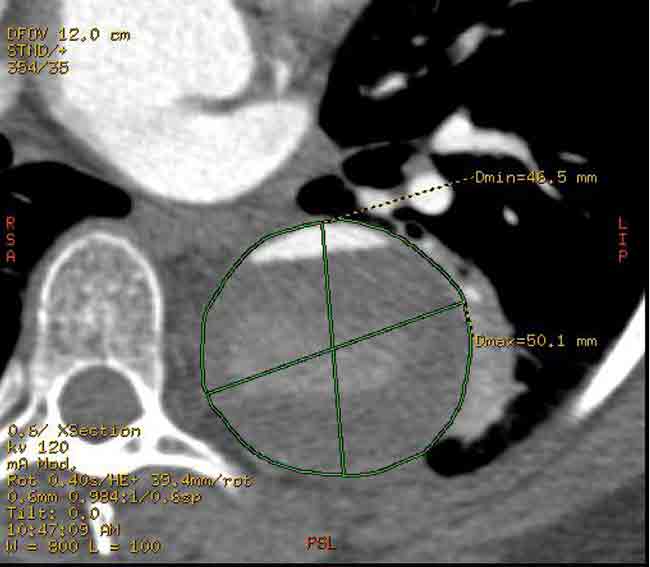

After performing a right groin cutdown and exposing the right common femoral artery, we exchanged our regular .035” guidewire for a stiff .035” guidewire. We used IVUS to confirm that the wire was entirely in the true lumen. We then inserted a 37 mm x 20 cm Gore TAG endoluminal graft over the guidewire and deployed it just beyond the left subclavian artery. We sized the diameter of the endoluminal graft based off of the diameter of the aorta just beyond the left subclavian artery. We allowed a 10% over sizing of the endoluminal graft to permit adequate proximal seal and fixation. Distally this would mean a significant oversizing of the endoluminal graft because the true lumen was significantly compressed. A completion aortogram demonstrated excellent seal proximally with no evidence of filling of the false lumen proximally. Distally there was some retrograde filling of the false lumen which is to be expected. The true lumen was also slightly expanded due to the oversizing of the endograft distally. With IVUS and aortography, we carefully inspected the septum distal to the stent graft above the celiac artery and there were no other signs of active communication between the two lumens.

Endovascular repair of patients with chronic Type B aortic dissection with associated aneurysm of the false lumen is a controversial subject. The most significant concern is gaining proximal seal and preventing continued expansion of the aneurysm. This case demonstrates the fundamental principles involved in choosing a stent-graft. The optimal diameter of the stent-graft should be matched to the diameter of the normal aorta proximal to the dissection. Minimal oversizing of the graft is necessary. At most there should be 10% oversizing. This minimizes the chance for graft infolding and for causing damage to the normal aorta from radial force of the stent-graft. The graft is secured by the dissection septum and unlike an aneurysm there is more contact of graft to aortic tissue. There is no need to taper the graft distally and the size of the graft is irrespective of the distal true lumen size. [4,5,6] In summary, the graft diameter should be sized to the proximal normal aorta and that diameter should be carried distally in the stent-graft despite the diameter of the distal true lumen.